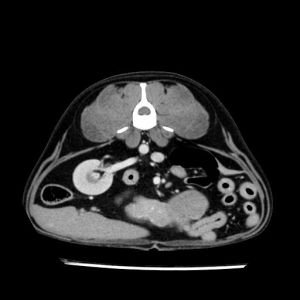

La lesione focale epatica , la ceus,la Tac e il chirurgo .